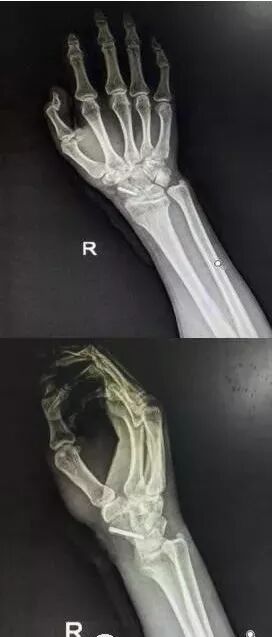

6)桡骨远端骨折

图片

• 绝大部分骨折可以手法复位制动。

• 关节面粉碎,塌陷者应手术。

• 如果伤后拇长伸肌腱卡压,正中神经损伤者,应立即手术。